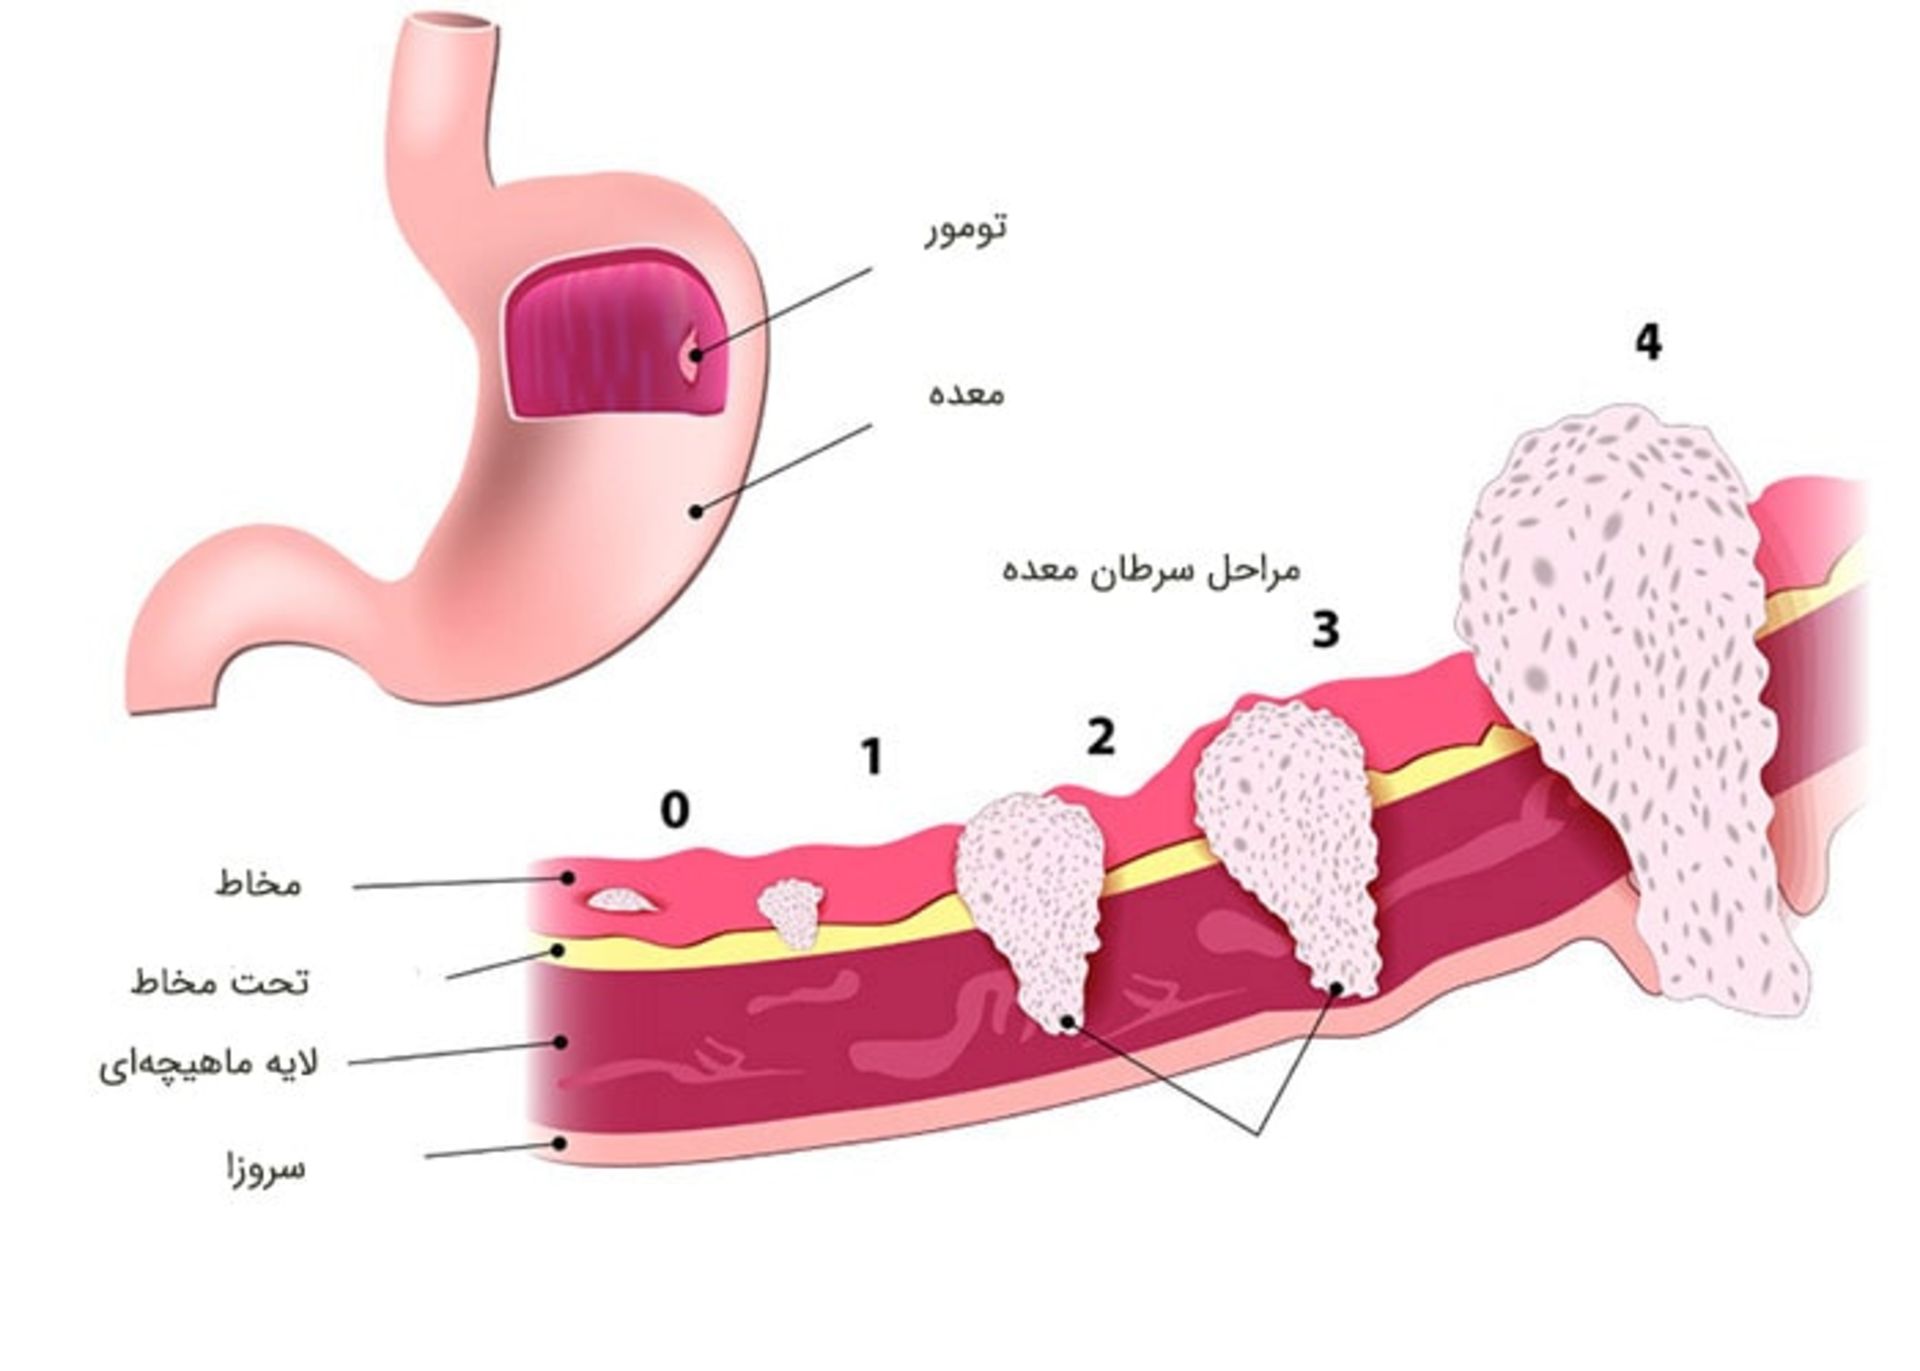

داخلیترین لایه، لایهی مخاط نامیده میشود که آنزیمهای گوارشی و اسید معده در آن ساخته میشوند. اغلب سرطانهای معده در این لایه آغاز میشوند. لایهی بعدی، لایهی تحت مخاط است. خارج از این لایه، لایهی آستر عضلانی (ماهیچهای) وجود دارد که لایهی ضخیم متشکل از ماهیچههایی است که با حرکات خود محتویات معده را با هم مخلوط میکند. دو لایهی خارجی یعنی لایههای تحت سروزا و لایهی سروزای خارجی، لایههای پوشانندهی معده هستند.

لایهها برای تعیین مرحلهی پیشرفت بیماری سرطان و تعیین پیشآگهی یک فرد مهم هستند. هرچه سرطان از لایهی مخاط به لایههای داخلیتر نفوذ میکند به این معنا است که سرطان پیشروی کرده و پیشآگهی آن چندان خوب نیست.

مراحل سرطان معده

بعد از اینکه وجود سرطان معده تأیید شد، پزشکان وضعیت سرطان را از لحاظ انتشار و وسعت انتشار مورد بررسی قرار میدهند. تعیین مرحلهی سرطان تشریح کنندهی وضعیت سرطان در بدن است. این امر به تعیین میزان وخیم بودن سرطان و اتخاذ بهترین روش درمان کمک میکند. مرحلهی ابتدایی سرطان معده مرحلهی صفر نامیده میشود و سپس وارد مراحل یک تا چهار میشود. بهعنوان یک قانون، هرچه عدد کمتر باشد، نشاندهندهی این است که میزان انتشار سرطان کمتر بوده است. عدد بیشتر مانند مرحلهی چهار نشاندهندهی انتشار وسیع سرطان است. اگرچه تجربهی هر فرد از سرطان منحصربهفرد است، سرطانها در مراحل یکسان دارای چشمانداز مشابهی هستند و اغلب به روش یکسانی مورد درمان قرار میگیرند.

سیستم تعیین مرحلهای که برای سرطان معده استفاده میشود، سیستم TNM است که براساس سه گروه از اطلاعات کلیدی انجام میشود:

اندازهی تومور (T): سرطان تا چه حد در پنج لایهی دیوارهی معده رشد کرده است؟ آیا سرطان به ساختارها یا اندامهای مجاور نیز رسیده است؟